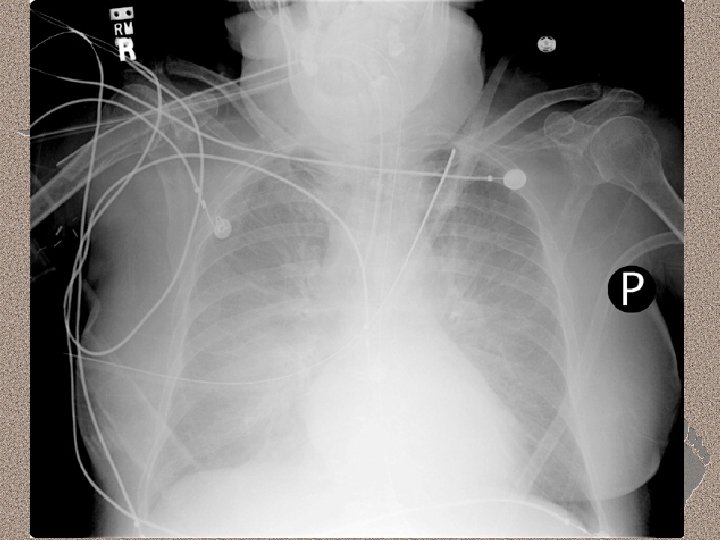

Pemeriksaan Penunjang • Laboratorium • AGD : alkalosis respiratorik pada fase awal, dan berganti menjadi asidosis respiratorik pada fase lanjut • Leukositosis (sepsis), anemia, trombositopenia (SIRS), peningkatan kadar amilase (pankreatitis) • Gangguan fungsi ginjal dan hati. • Pencitraan • • Foto dada : gambaran radioopak difus CT-Scan : pola heterogen, predominasi infiltrat pada dorsal paru (supine)